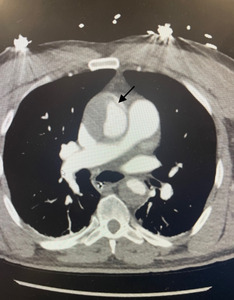

Patient CT angiogram of the chest revealed a type A thoracic aortic dissection that extended throughout the entire ascending and descending thoracic aorta and into the proximal abdominal aorta. The radiologist called with these results and we then placed an emergent consultation to our facility’s cardiothoracic surgery team. After speaking with the surgeon over the phone, plan was made for the patient to urgently go to the operating room for repair. MRIs were then canceled.